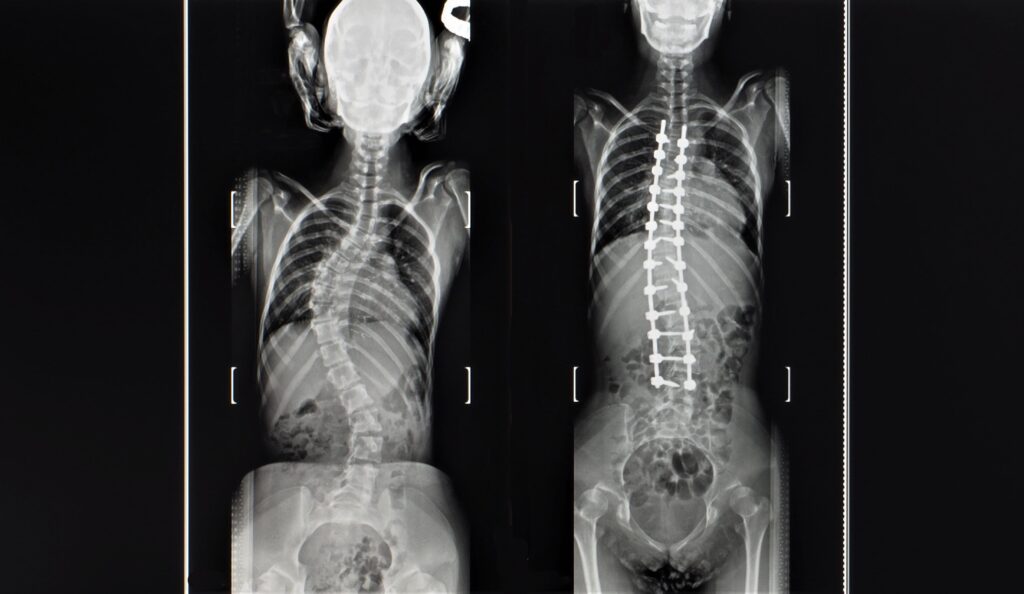

There are also some conditions that may require a referral to another specialist. For example, if you have cancer or an infection, you will likely be referred to a doctor who specializes in treating those conditions. Another condition that generally requires surgery is moderate to severe spinal deformities. In some cases, a neurologist may also refer you to a spinal surgeon if your back pain is severe and does not respond to other treatment options. There are simply some cases of back pain that respond better to a more invasive, surgical approach.